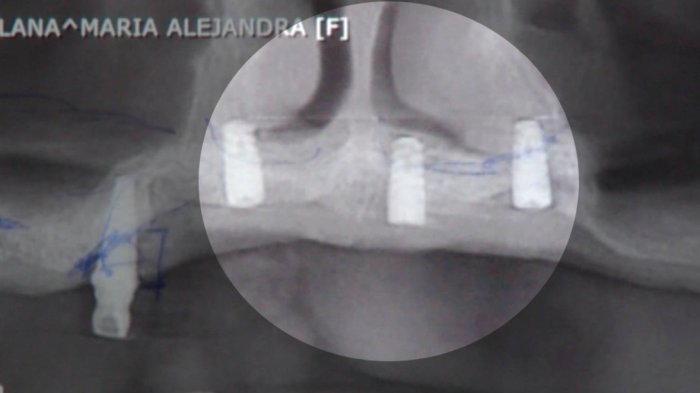

El cirujano plástico Juan Pablo Cisternas, aconsejó el chequeo temprano y constante de mamas, además de un llamado a la calma tras la alerta de la FDA en Estados Unidos por la detección de implantes presuntamente dañinos como causa un tipo de cáncer mamario.